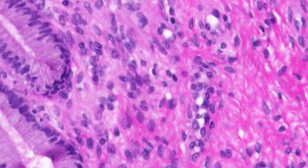

Figure 1 shows samples for 20 classes of Kimia Path960 dataset. In spite of the large texture variability, one can spot some inter-class similarities which may affect the classification. Figure 2 illustrates the large intra-class variability which is another challenging aspect of this dataset.